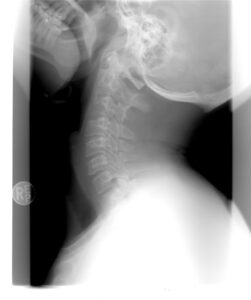

Now weeks or months later you are still suffering, even though normal muscle, tissue, joint, and bone healing time has well passed. Life is becoming more consumed with this pain such that you finally seek help. The doctor takes a picture of your spine (or body part) before they even talk with you or touch you. Then BANG- THERE IT IS- the root of your problem. See that tiny “bulge” there- that is why you hurt. Oh, plus you have this degeneration of your spine (or pick the body part) there- that is the worst. I forgot to preface this with the fact the patient is 55 years old so these findings are NORMAL.

Back to imaging not telling the whole story. So now we know age changes on the inside are normal. And we know it is possible to have pain outside of normal tissue, muscle, etc damage or injury. So what is left? To turn you back into the person with WHATEVER may appear on an image but WITHOUT the pain. This is the #1 goal I work with patients on.

No, it is not necessary to see those images because they do not answer the question of how best to treat you or help you feel better. The real story comes from you, the patient (not some image). All I care about it how you move, function, your goals and more. Learning about you, helps someone like me create a plan to help you achieve your goals. Addressing strength, flexibility, coordination, and yes even sometimes psychology or pain sciences are part of helping you feel better.